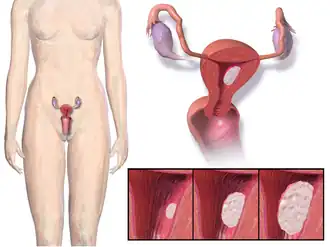

| Localização e desenvolvimento do cancro do endométrio. | |

Cancro do endométrio (português europeu) ou câncer endometrial (português brasileiro) é o cancro que tem origem no endométrio, o revestimento do útero.[1] A doença é o resultado do crescimento anormal de células com a capacidade de invadir ou de se alastrar para outras partes do corpo.[8] O primeiro sinal é geralmente uma hemorragia vaginal sem estar associada a um período menstrual; os outros sintomas incluem dor ao urinar ou durante o acto sexual ou dores pélvicas. O cancro do endométrio ocorre com maior frequência depois da menopausa.[2] Este cancro é muitas vezes referido como "cancro do útero", embora seja distinto de outras formas de cancros do útero, como o cancro do colo do útero, sarcoma uterino ou doença trofoblástica.[9]